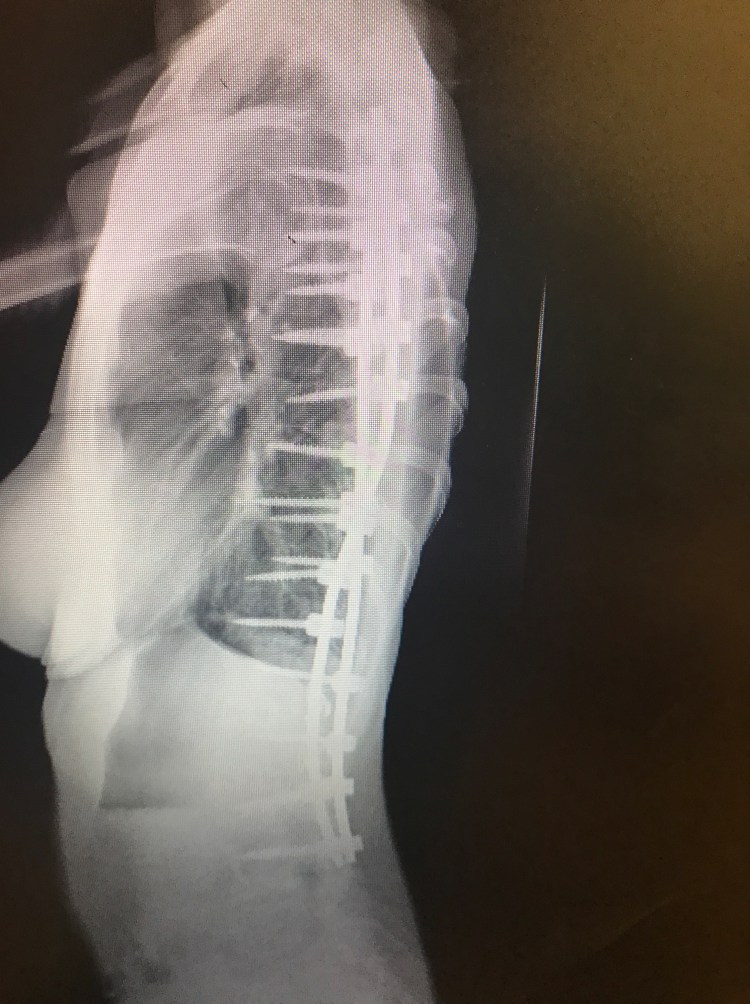

Last week, on Will’s birthday, it was also my 5 month post op appointment. I had a long list of questions and concerns and I was extremely anxious. These appointments always make me nervous and give me anxiety. While in the car on the long drive there, I can’t help but think about everything that happened and how it is going to affect me for the rest of my life. The feeling of these long rods screwed into my spine will never go away although hopefully get easier to forget about over time. I will never be able to bend my back or twist or bend side to side EVER. I still get asked this on a daily basis. The answer is never. Then, I have to continue to be cautious and not slip or fall or do anything that could cause a screw or rod to break and hope upon hope that these rods and screws can last the duration of my life without needing to be replaced. I already know somewhere in the future I will need another surgery to fuse the last few levels to my pelvis and boy am I already dreading for that day to come. Sorry to be a Debbie Downer. I guess it’s hard when people think because I am back at work, or can drive Will to preschool or wrap some damn Christmas presents that I must be “better”. Anyways…..my Doctor said that my bones are fusing. One side is fusing better than the other, but she is hopeful that the other side will catch up. She thinks that the first few months and all the added stress on my body prohibited me from really recovering until just recently. Fusions also can take up to 2 years from surgery to heal completely. All my screws are in place as well. We agreed I need to continue with physical therapy. Last week, I began light core muscle exercises with some resistance to help build my stomach muscles back up. Right now, I am having trouble standing up all the way do to the tightness in my hips and hamstrings. When I am not standing straight, it causes my back muscles to fire up causing some pretty crappy back pain. There’s still a long way to go to get this leg working and my shoulder is still causing me trouble as well. I am also still having blackout and dizzy spells which we had attributed to medicine, however, since being off everything for the most part, I am still having these multiple times a day. I was told I need to see a neurologist and get a primary doctor to run some tests.

You look great. Your xrays look even straighter now!!! Do you live in Cali? Im trying to figure that one out because your dressed like its cold and i thought you lived in Cali. Who was your surgeon again.? God Bless. Your a strong woman and sounds like you have a great supportive husband.

Yes in Northern California. Our weather can be in the 100’s in summer and in the 30’s in Winter. My back is actually a little less straight than right after with settling, but definitely staying put and starting to fuse!